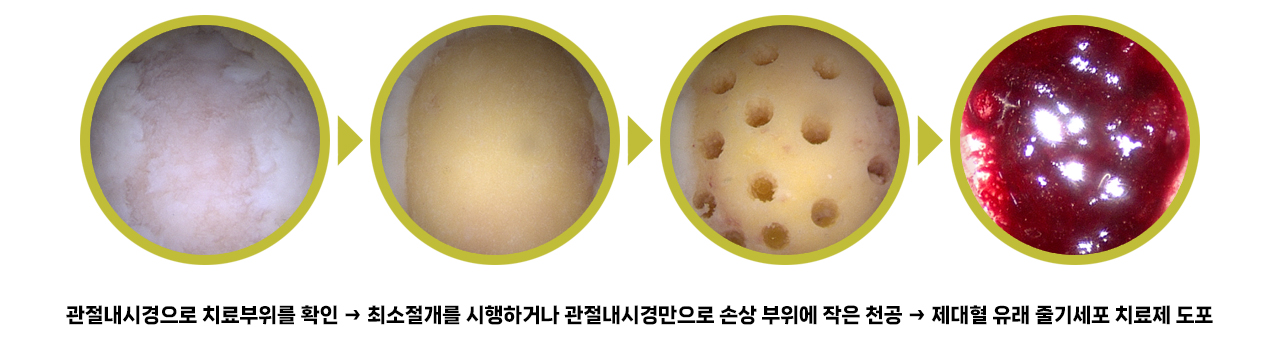

제대혈 유래 줄기세포 치료과정

치료 사례

관절내시경이나 최소절개를 하여, 제대혈유래 줄기세포 치료제(카티스템)를 도포하여 치료

제대혈 유래 줄기세포 치료의 장점

- 모든 연령층에서 연골재생효과를 누릴 수 있음

- 1회의 치료만으로도 탁월한 연골재생효과를 기대할 수 있음(개인차 있을 수 있음)

- 연골결손 크기가 큰 경우에도 연골 재생효과가 뛰어남